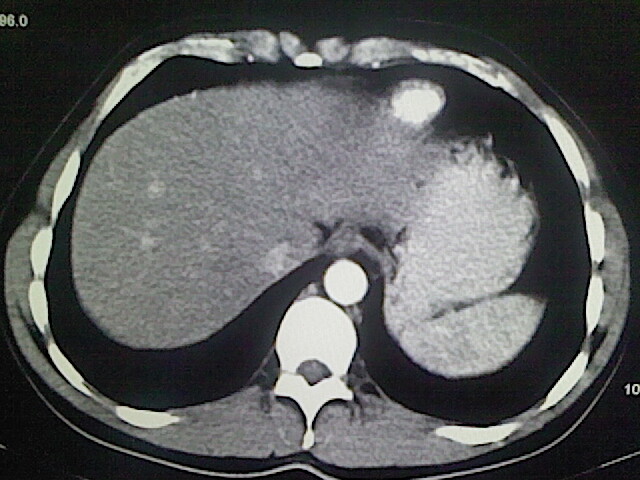

以下是引用卜一在2009-3-14 9:49:00的发言:[br]胆囊萎缩,胆囊壁不规则增厚,内部结构模糊,增强明显强化。另:肝左叶外侧段肝囊肿。支持:慢性胆囊炎!高度可疑:胆囊癌!

以下是引用余辉在2009-3-14 8:48:00的发言:[br]1)慢性胆囊炎。2)肝左叶外侧段肝囊肿。3)脂肪肝。[br]支持,胆囊萎缩,密度增高,不知b超具体有何提示,钙胆汁?结石?

以下是引用jiangjing在2009-3-14 10:18:00的发言:[br]1)慢性胆囊炎。2)肝左叶外侧段肝囊肿。3)脂肪肝。4.】建议行肝功能检查